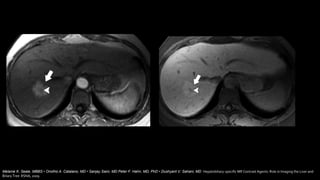

Contraste hepátoespecifico

Melanie K. Seale, MBBS • Onofrio A. Catalano, MD • Sanjay Saini, MD Peter F. Hahn, MD, PhD • Dushyant V. Sahani, MD Hepatobiliary-specific MR Contrast Agents: Role in Imaging the Liver and

Biliary Tree RSNA, 2009